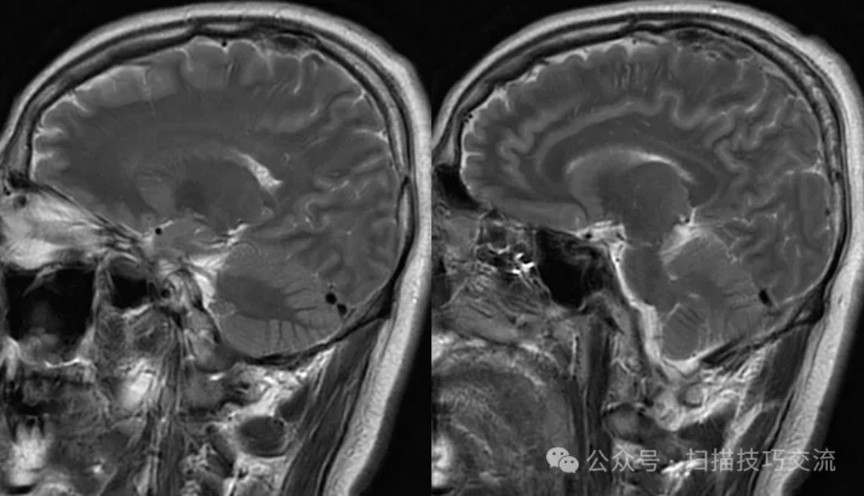

•男性,29岁,已婚 •头痛伴头晕恶心呕吐20余天 •现病史:患者于20天前,熬夜饮酒后出现头痛,为胀痛,头痛剧烈,伴头晕恶心呕吐。就诊于当地医院,未作出明确诊断。现症状有所缓解,于平卧位时无明显不适,坐位或直立式上述症状加重。急诊以“头痛”收入卒中中心。病程中无视物模糊,无饮水呛咳,无吞咽困难,无抽搐发作等症状。自发病以来睡眠欠佳,近3日未进食,二便正常。近期体重未见明显变化。 •既往史:平素健康,过敏史或不良反应药物反应史无。外伤史无。手术史无。传染病史无。预防接种史无。其它无。

•汗腺分泌:正常,皮肤划痕正常反应。 •尿便障碍:无。性功能障碍无。 •专科情况:正常。不逐一罗列。 •辅助检查:01-05颅脑CT提示:1,上矢状窦、双侧横窦密度较高,请结合临床,必要时进一步检查;2,双侧脑室后角可疑稍高密度影,右顶叶局部脑沟密度可疑增高,建议进一步检查。 •初步诊断:静脉窦血栓

临床申请:颅脑平扫,静脉成像,磁敏感成像,颅内静脉血管黑血成像。

图像不逐一罗列,未见异常。